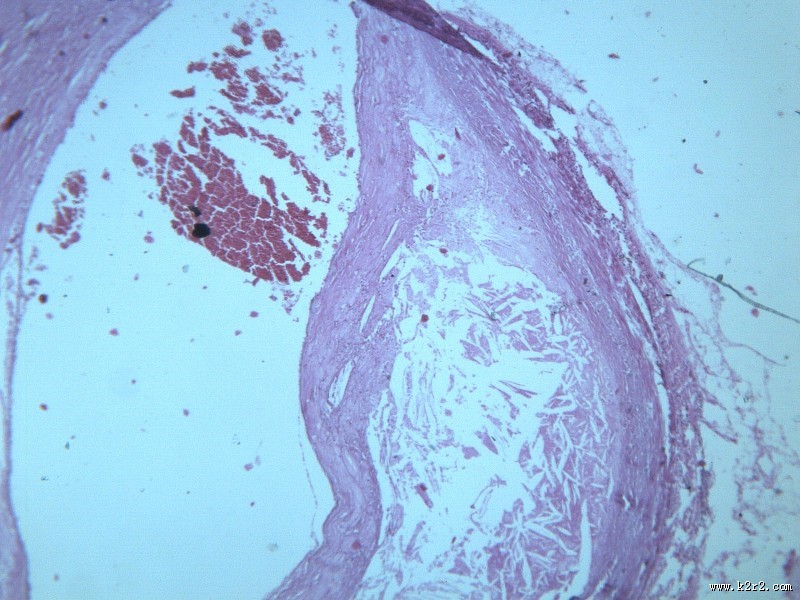

首页 > 其他类别 > 动脉粥样硬化(12张) > 动脉粥样硬化 第2张

动脉粥样硬化 - 第2张